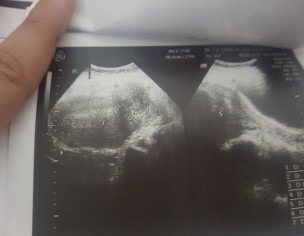

these r my ultrasound report should i go for surgery?? ak br mai ny expect kia ha par result was explusion in 24 weeks plzz guide me im not conceiving again